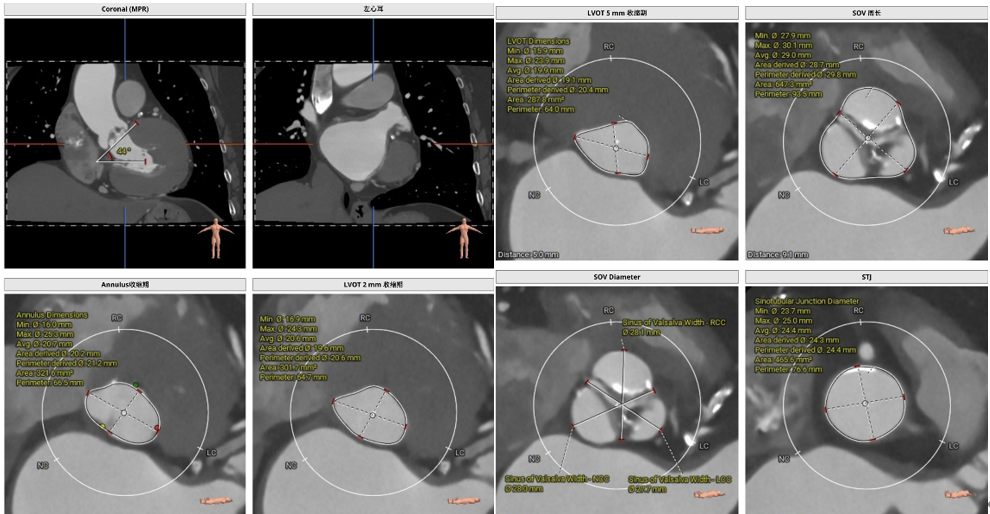

二.TAVR术前CT评估(图3-5):

Type1(LN)型二叶式主动脉瓣,瓣叶轻度钙化并增厚,钙化分布不均匀;双侧冠脉开口高度可;瓦氏窦可、窦管交界可、升主动脉可、左室心腔内径可;主动脉瓣环水平夹角41°;双侧髂股走形可, 双侧髂股动脉内径可。全面评估后决定在导管室、局麻下行极简式TAVR。

(图3)

(图4)

(图5)